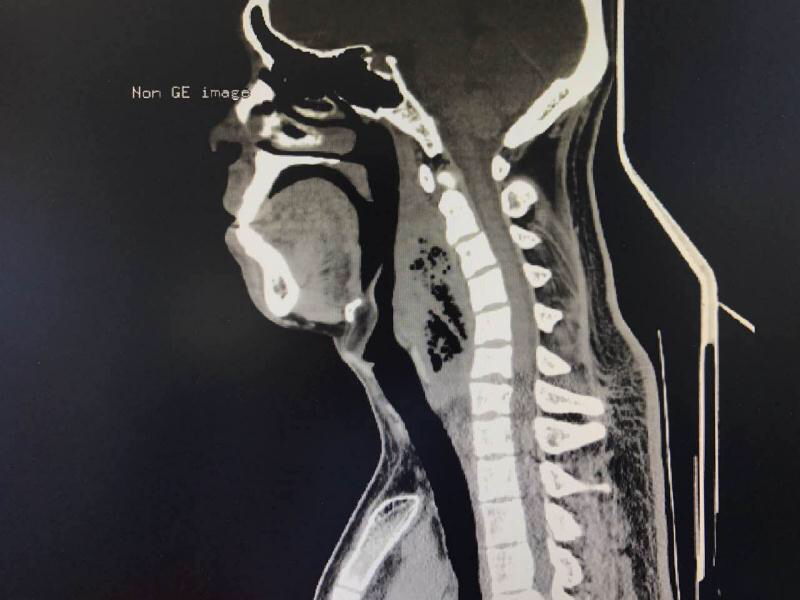

近日,小陈来到了沈阳市第四人民医院就诊,耳鼻咽喉科门诊王国新主任通过喉镜检查,发现患者咽喉壁隆起明显,急诊为患者行CT检查。CT显示:咽后壁及颈部可见巨大的脓肿,脓肿内还有大量的气体影——颈深部脓肿。这是一种非常凶险的疾病,可以发展成坏死性筋膜炎,亡率非常高。任何医生都会觉得非常棘手。

凌晨三点,手术开始,深夜的手术室一片寂静,只有监护仪不时发出来的滴滴声。而病情的凶险却让手术室的空气中弥漫着紧张的气氛。患者的下咽侧壁膨胀明显,相邻的肌肉筋膜组织已经被侵袭,每推迟一分钟都有发生破溃的可能。如果破溃的脓液一旦流入颈部的筋膜间隙,就会发生坏死性的筋膜炎,那是一种死亡率相当高的疾病。当切开脓肿的那一刻,散发恶臭的脓液随着吸引从脓腔流出。这是多种细菌混合感染的一种疾病,里面还有能产生气体的厌氧菌,对组织的破坏力极大,病情进展特别迅速。